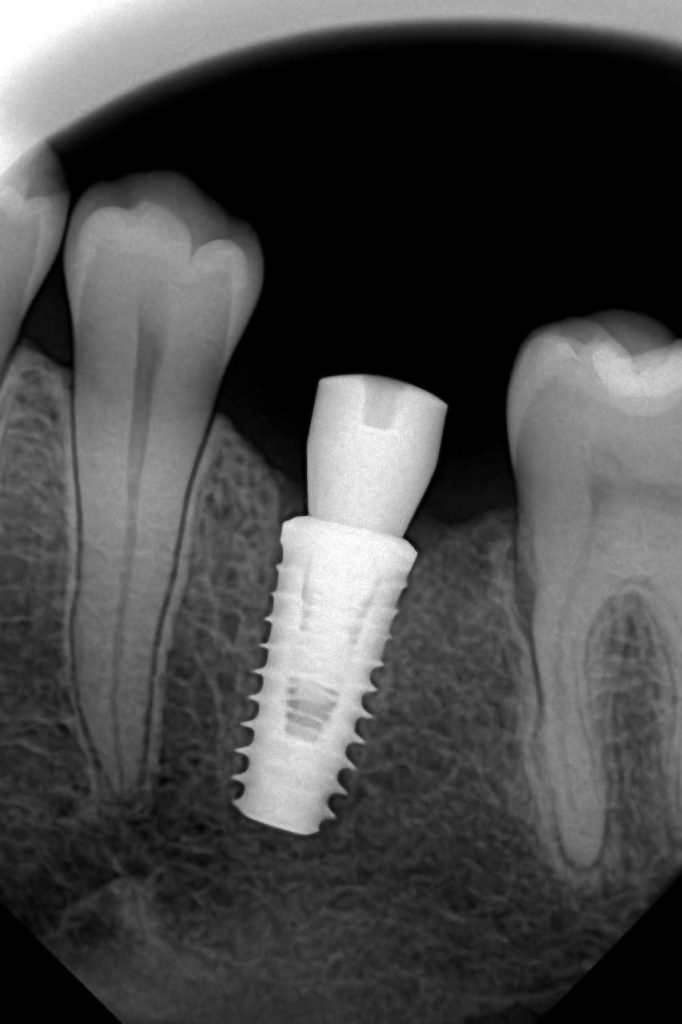

The prosthesis was seated under magnification to verify complete adaptation and marginal integrity. The screw channel was filled with PTFE and sealed using composite resin.

5. Post-Insertion Evaluation

Contacts and occlusion were refined to achieve even force distribution. Radiographic verification confirmed a passive fit and absence of any marginal discrepancies or bone loss.

- Bone levels: Stable, with no radiolucency at the crestal margin.